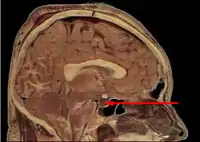

If secondary adrenal insufficiency is diagnosed, the insulin tolerance test (ITT) or the CRH (corticotropin-releasing hormone) stimulation test can be used to distinguish between a hypothalamic (tertiary) and pituitary (secondary) cause but is rarely used in clinical practice.[17]

In some cases, the actual cause of low ACTH is from low CRH in the hypothalamus. It is possible to have separate ACTH and CRH impairment such as can happen in a head injury.[18]